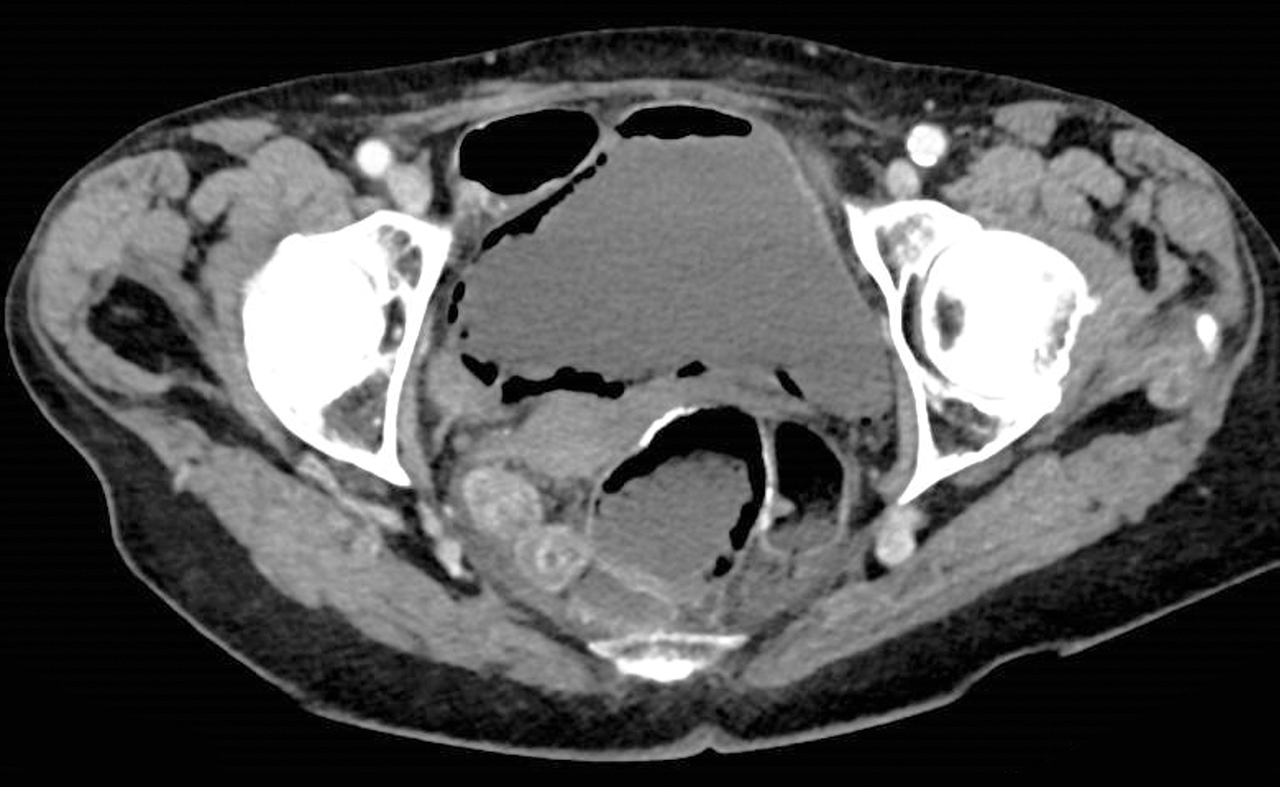

Une femme de 89 ans est hospitalisée pour une fièvre et des douleurs abdominales.

Quel est votre diagnostic ?